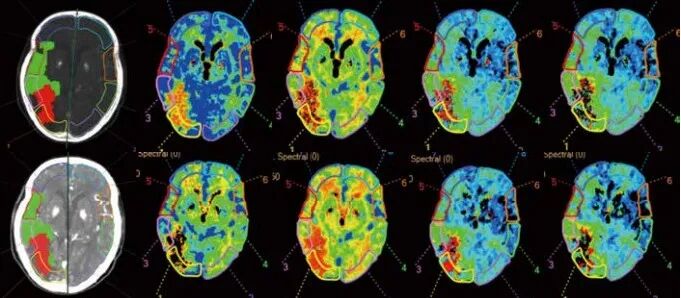

在脑卒中全流程评估方面,该CT能够1分钟内CT平扫诊断超早期脑梗塞,极速缩短了脑卒中诊疗流程,实现从超早期发现脑梗、指导治疗以及术后评估疗效全流程精准影像诊断。在判断脑卒中病变的同时,可同步对颈部斑块成分、危险程度等进行定量、定性分析,并对颈部斑块和脑卒中病变之间的关系进行准确判断。对于检查时间要求较高的急诊病人来说,非常有益。